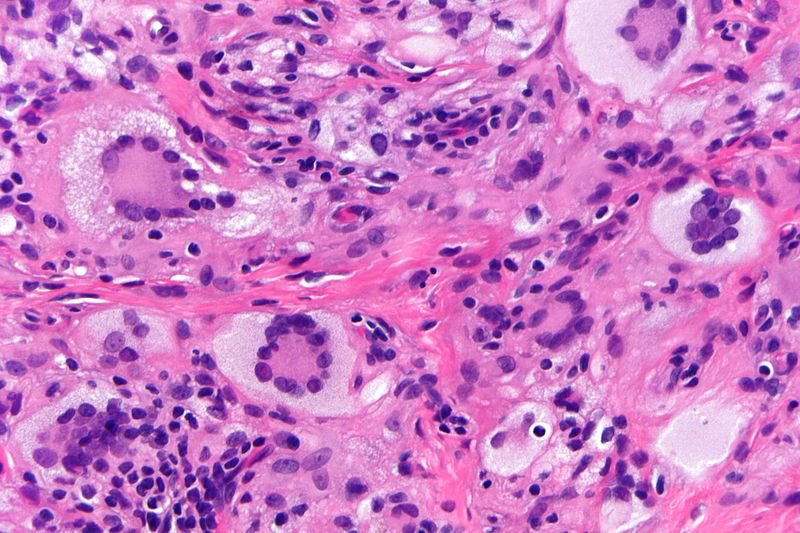

The following image shows large cells in the epidermis with a clear halo, which are characteristic of _____ disease